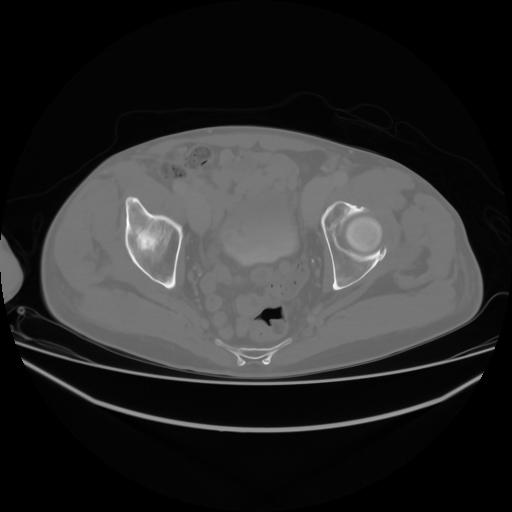

4 CUERPO,CE,Axial,3.0,CUERPO,,